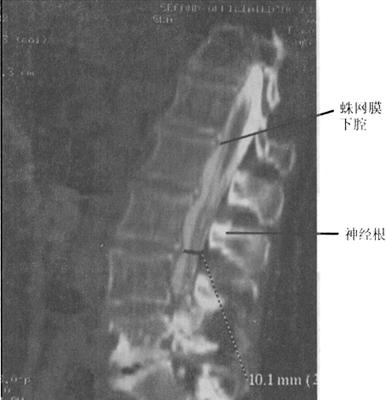

(四)CT脊髓造影或脊髓造影后CT

CT与MR出现以来,脊髓造影已不再常规使用。但在复杂的脊柱损伤CT扫描中,无法显示硬膜囊内结构,使用水溶性非离子型鞘内造影剂进行脊髓造影后CT扫描(CTM)扩展了CT在脊髓损伤中的应用(图7-11)。

图7-11 脊髓造影后多排螺旋CT扫描矢状面重建,可区分脊髓、神经根。蛛网膜下腔充满造影剂呈高密度,而脊髓、神经根呈中等密度

传统的脊柱造影需要病人配合医生转动体位来控制造影剂在椎管里的流动,而对脊髓损伤的病人,这可能是致命的危险,俯卧位似乎比侧卧位及仰卧位更易导致椎骨脱位。CrM对神经系统损伤病人的术前评估更有价值。当MR成像更普及时,脊髓X线摄影术和CTM的运用将逐步减少。

当脊髓、马尾神经被软组织压迫或怀疑硬脊膜撕裂时,CTM扫描就显得特别有用。一般来说,鞘内注射造影剂是通过C1~C2穿刺,以减少搬动病人所带来的潜在损伤。CTM的优点在于:①脊髓更好地显影;②提高软组织损伤压迫脊髓的诊断显示率,例如椎间盘突出或硬膜外血肿;③脊髓神经根的硬膜撕裂的诊断。CTM较之传统X线体层摄影、脊髓造影和CT平扫在脊椎骨折损伤的神经定位方面有较大的优越性。脊髓压迫可以在X线脊髓造影中显示,但在CTM中显示更清楚直观。在严重压迫的情况下,髓内创伤的诊断是非常困难的。硬膜外不同程度的压迫可导致脊髓不同程度的破裂。当造影剂充盈硬膜囊时,严重的脊髓损伤可出现脊髓缺损的征象。硬膜撕裂可导致造影剂外渗至硬膜外间隙。尽管撕裂的硬膜可自愈,但识别硬膜撕裂也是很重要的,因为撕裂可能导致多种后遗症,如脑膜炎、神经根内陷,脑脊膜突出或延迟神经损伤。CTM在全脊髓损伤病人诊断中的作用仍存在争议。